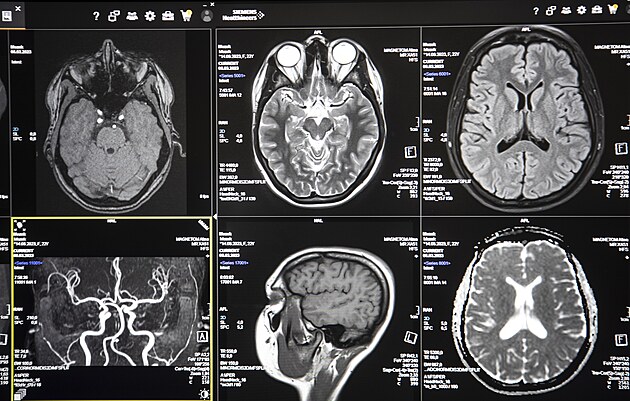

Fakultní nemocnice Královské Vinohrady (FNKV) zahájila provoz nového přístroje magnetické rezonance Siemens Magnetom Altea. Moderní software umožňuje komplexní vyšetření. (15. června 2023)